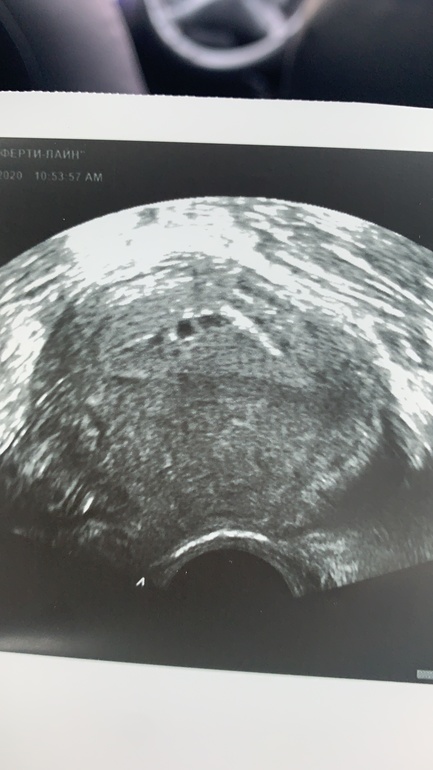

Кто-то что-то видит? Такие чудеса